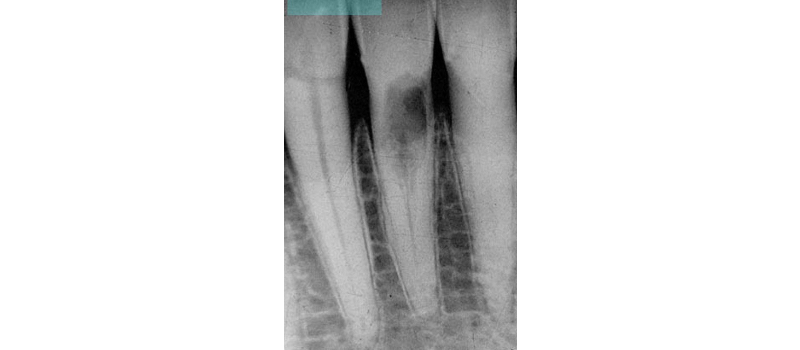

What’s unique about this type of root resorption is that it does not invade the pulp. In fact, the pulp in these teeth remains vital, and the resorption tends to navigate around the pulp canal (hence the alternate designation of extra-canal invasive root resorption). Radiographically, even with extensive cases of invasive cervical root resorption, you can still visualize an intact canal space (Fig. 2).